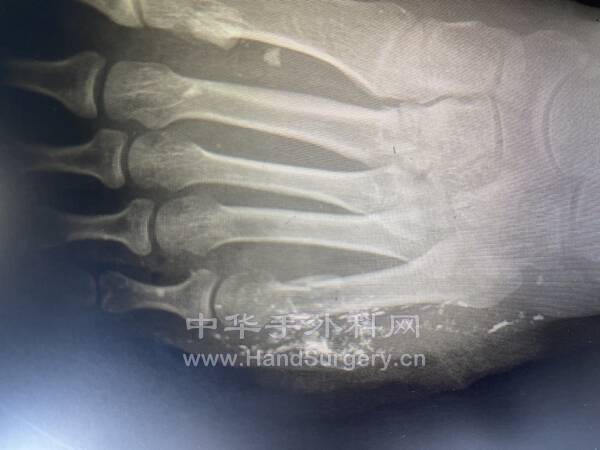

mmexport1628470422479.jpg

mmexport1628470404142.jpg

mmexport1628470410598.jpg

饺子粉+克氏针妙用